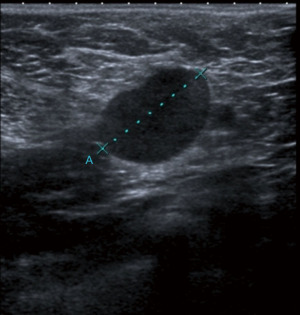

Breast cancer usually appears in ultrasound as hypoechoic (dark) mass with irregular margins, with vertical orientations and/or accompanied by posterior, acoustic shadowing. Some tumours can have an infiltrative pattern of growth appearing as non-circumscribed areas of decreased echogenicity (darker than normal parenchyma) (Figure 4). Ultrasound reliably differentiates between cystic and solid lesions.